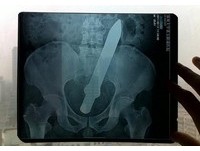

自慰器的歷史與演進已有段時間,雖然有不少人認為古代中國這麼傳統保守並封建的國家是不會發明或敢於使用這類東西,所以應該是原創於西洋再傳進中國。但根據考古學家的研究指出,無論是男性或女性自慰器,在歷史記載裡最早發明與使用的國家其實是中國。 《詳全文...》